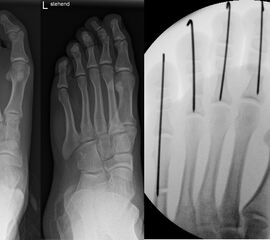

Chevron Osteotomie

Die Chevron Osteotomie 1 ist ohne Komplikationen am wachsenden Skelett durchführbar. Das Metatarsale I besitzt distal keine Wachstumsfuge, die geschädigt werden könnte. Die „französische Methode nach Marc Elkaim“ eignet sich für Kinder ganz besonders (Abb. 28).

Abb. 28 a-g: Radiologischer Verlauf einer Chevronosteotomie nach dem Verfahren von M. Elkaim mit prä- (a-c drei unterschiedliche Ansichten) und intraoperativen Röntgenbildern in zwei Ansichten (d-e) sowie postoperativ zwei Ansichten (f-g).

Zum Lesen der Bildbeschreibung und zur Vollansicht bitte die Bilder anklicken. Bilder: A. Helmers.

Sie wird über eine eigene Tapetechnik fixiert und kann bei einem erhöhten Intermetatarsale-Winkel alternativ zur Scarf-Osteotomie durchgeführt werden. Nachteile der Methode sind eine deutliche Verkürzung durch die Fräse sowie eine starke Plantarisierung des Metatarsale I Köpfchens. Um die Verkürzung zu vermeiden, wird verlängernd in Richtung des Metatarsale II Köpfchens (nicht wie offen in Richtung Metatarsale IV Köpfchen) osteotomiert. Gleiches gilt für die starke Plantarisierung, die durch den Knochenverlust der Fräse entsteht. Die Korrektur eines kindlichen oder jugendlichen Hallux valgus ist mit der Methode ansonsten suffizient durchführbar. Wird verkürzt, muss ausreichend plantarisiert werden, um eine Transfer-Destabilisierung MT II-IV zu vermeiden.

Die MICA-Technik sollte bei geschlossenen Fugen mit einem weitem intermetatarsale Winkel durchgeführt werden. Die dafür typische Verschraubung der Osteotomie kann bei geschlossenen Fugen ohne Probleme erfolgen. Diese Osteotomie kann gut mit einer Akin- und den beschriebenen Kleinzehen-Osteotomien kombiniert werden.